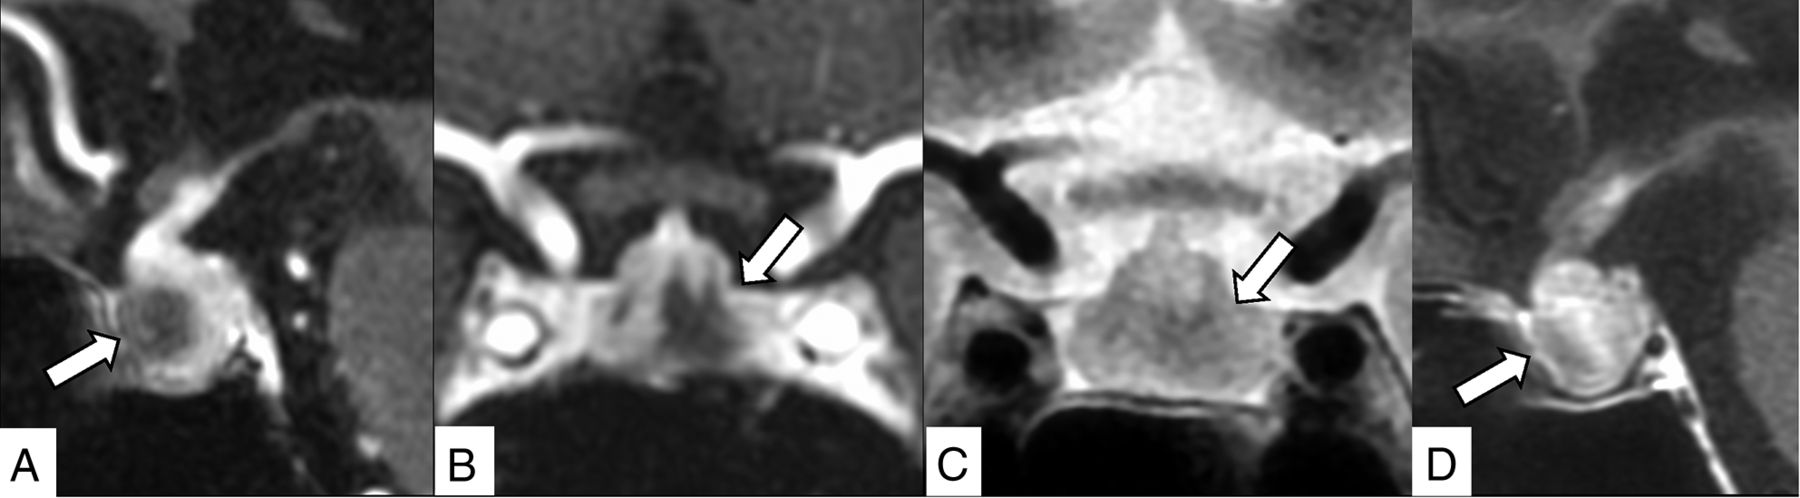

A 40-year-old woman receiving nivolumab plus ipilimumab for stage IV melanoma with corticotropin deficiency, hypothyroidism, and hand edema for 10 days. Contrast-enhanced 3D-MR imaging (90 seconds after contrast medium injection) demonstrates an enlarged pituitary gland and stalk and bilateral linear hypoenhancing lesions (A, sagittal reconstruction; B, coronal reconstruction, arrows). These lesions show hypointensity on the T2-weighted coronal image (C, arrows), and gradual enhancement is demonstrated in contrast-enhanced 2D coronal MR imaging performed 90 more seconds after the 3D MR imaging (D, arrows).